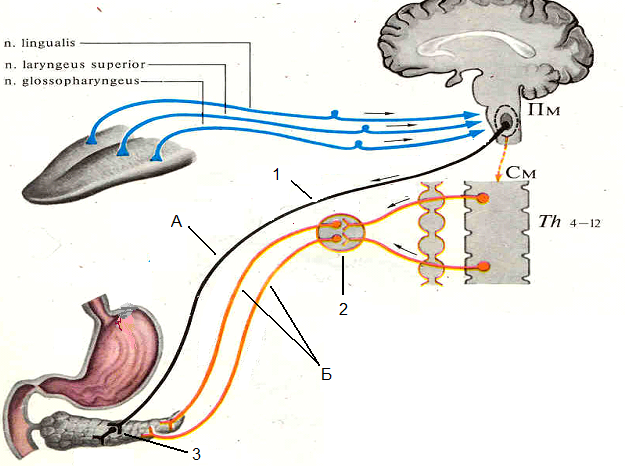

Как работает центр насыщения в гипоталамусе: визуальные иллюстрации